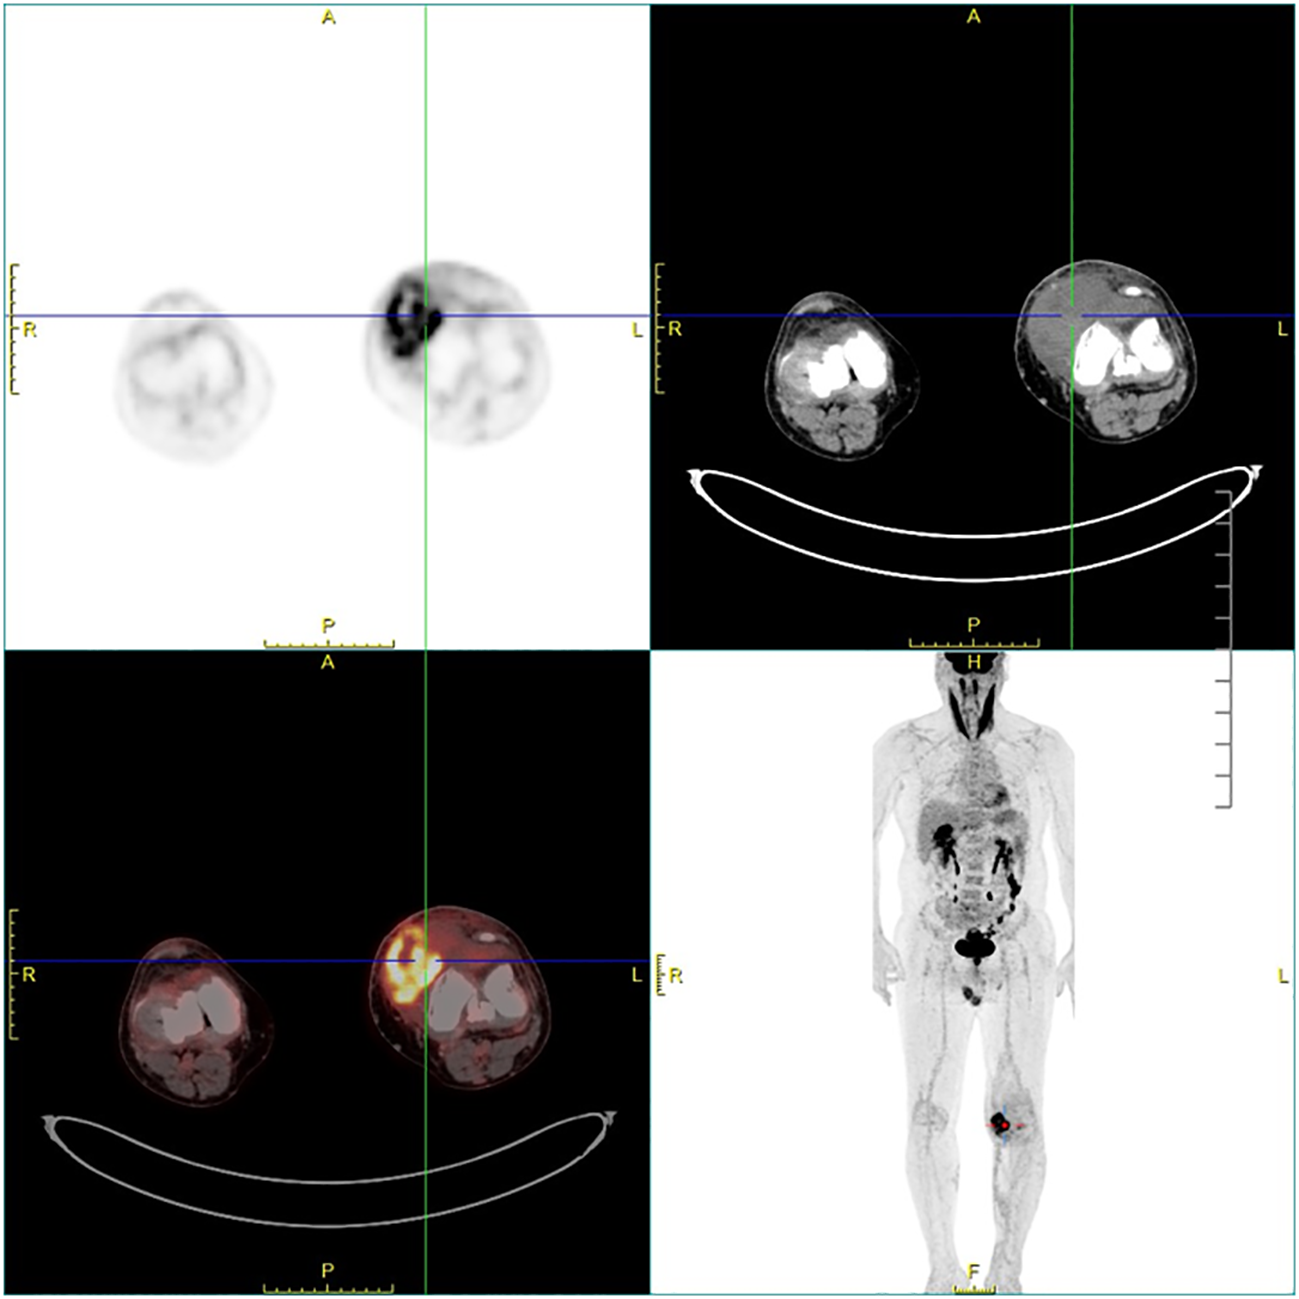

Figure 4

Fluorodeoxyglucose F18 (F-18 FDG) PET-CT showing an active heterogeneously enhanced mass in the joint cavity of the left knee.

Ethics approval for this study was granted by the Institutional Review Board of our hospital. A 60-year-old man was admitted to the Department of Orthopedics of our hospital due to swelling in the left knee for the past 8 months. The patient had no history of relevant trauma and had no other complaints of discomfort. The skin and the temperature of the left knee were normal. X-ray of the left knee was first taken (Figure 1), which showed soft tissue swelling mainly on the anteromedial side of the knee, where the density was higher than that of normal soft tissue. Moreover, some strip calcification could be seen in the X-ray, but there was no destruction of the bone. To further define the lesion, the radiologist recommended CT or MRI. Enhanced CT and MRI were both performed, which confirmed the irregular soft tissue mass within the joint cavity of the left knee. CT of the left knee (Figure 2) showed that the calcification in the mass was mainly located at the edge. After injection of a contrast material, the enhancement was heterogeneous, and a nodular enhancement of the lesion was presented. Small enhanced vessels could be seen in and around the mass. There was no destruction to the adjacent bones. MRI presented the shape of the lesion better (Figure 3). The mass was irregular, and it appeared to grow along the synovial membrane of the joint and was partly nodular. On T2-weighted images (T2WI), the lesion was hyperintense. On T1-weighted images (T1WI), the lesion was mainly hypointense, but with some nodular hyperintensity. In the enhanced images, the lesion showed a markedly heterogeneous enhancement, especially the nodules. The margin of the lesion was unclear. The adjacent medial collateral ligament of the left knee was swollen and was partly invaded by the mass. Edema was evident in the soft tissue surrounding the mass. It was difficult to determine what the lesion was; therefore, a needle biopsy was performed, which suggested malignancy. F-18 FDG PET-CT, which was performed for tumor restaging, revealed active heterogeneous enhancement of only one tumor, with a maximum standardized uptake value (SUVmax) of 7.51 (Figure 4). No other metabolically active lesions were seen in the body; therefore, the patient underwent surgical resection. The soft tissue and muscle around the tumor were separated, and the distal femur and the proximal tibia and fibula were excised for complete resection of the tumor. Subsequently, knee prosthesis replacement was performed. The whole operation was successful. Postoperative pathology confirmed malignant SFT with focal necrosis. Immunohistochemical examination revealed that the neoplastic cells were positive for CD34, Bcl-2, and SATA6 (Supplementary Figure S1). The immunohistochemistry results were as follows: CD34 (partially ++), Bcl-2 (partially ++), STAT6 (weak +), EMA (focal +), desmin (−), S-100 (−), beta-catenin (focal +), SMA (focal +), CK(AE1/AE3) (scattered +), CAM5.2 (scattered +), and Ki-67 (30% +). Approximately 11 months after surgery, the patient came to our hospital again due to bone abnormalities, and it was confirmed by imaging examination and puncture pathology that the patient had multiple bone metastases (Supplementary Figure S2).

Calcification is rare in SFTs. In our case, the calcification was patchy and located at the edge of the mass, which made it more difficult to distinguish from synovial sarcoma, which typically presents as a mass around large joints with obvious mixed signals and eccentric calcification occurring in young adults. Different forms of calcification in SFTs have been reported previously, including tiny, scattered, partial, or prominent calcification (27, 36, 37). Some researchers believe that calcification could be regarded as an indicator of malignancy (38), but its reliability has not been proven. In our case, the F-18 FDG PET-CT showed good uptake in the primary tumor and no other lesions were detected, which helped in the staging. There are only a few descriptions in the literature with regard to the PET manifestations of SFTs. It was found that benign SFTs exhibit low-grade activity in PET and that malignant SFTs tend to be strongly hypermetabolic and homogeneous (10).